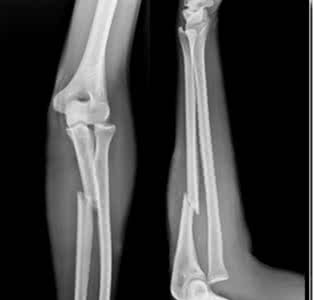

本病的辅助检查主要是X线检查。肘关节侧位X线片,可准确掌握骨折的特点。前后位X线平片也很重要,它可以呈现骨折线在矢状面上的走向。若桡骨头也同时发生了骨折,在侧位X线片上可以沿骨折线出现明显断缩,并且没有成角或移位。